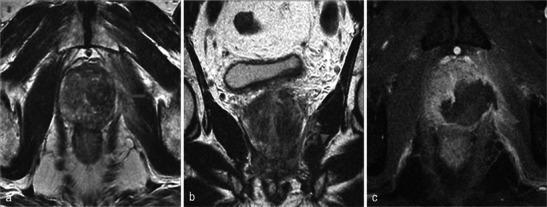

In this technique, a photosensitising agent is introduced intravenously, then activated by local laser illumination to induce tumour necrosis. Treatment efficacy is assessed by magnetic resonance imaging (MRI).

We illustrate specific post-treatment MRI aspects at early and late follow-up with pathological correlations.

• Dynamic phototherapy is a new and promising focal therapy for prostate cancer. • One-week MRI shows increased volume of the treated lobe and large, homogeneous necrosis area. • Six-month MRI shows significant changes of the prostate shape and signal. • Six-month MRI becomes "base line" appearance for further follow-up or monitoring.

• 动态光动力疗法是一种用于前列腺癌的新型且有前景的局部治疗方法。• 一周后的MRI显示治疗叶体积增大以及大片均匀的坏死区域。• 六个月后的MRI显示前列腺形态和信号有显著变化。• 六个月后的MRI成为进一步随访或监测的“基线”表现。